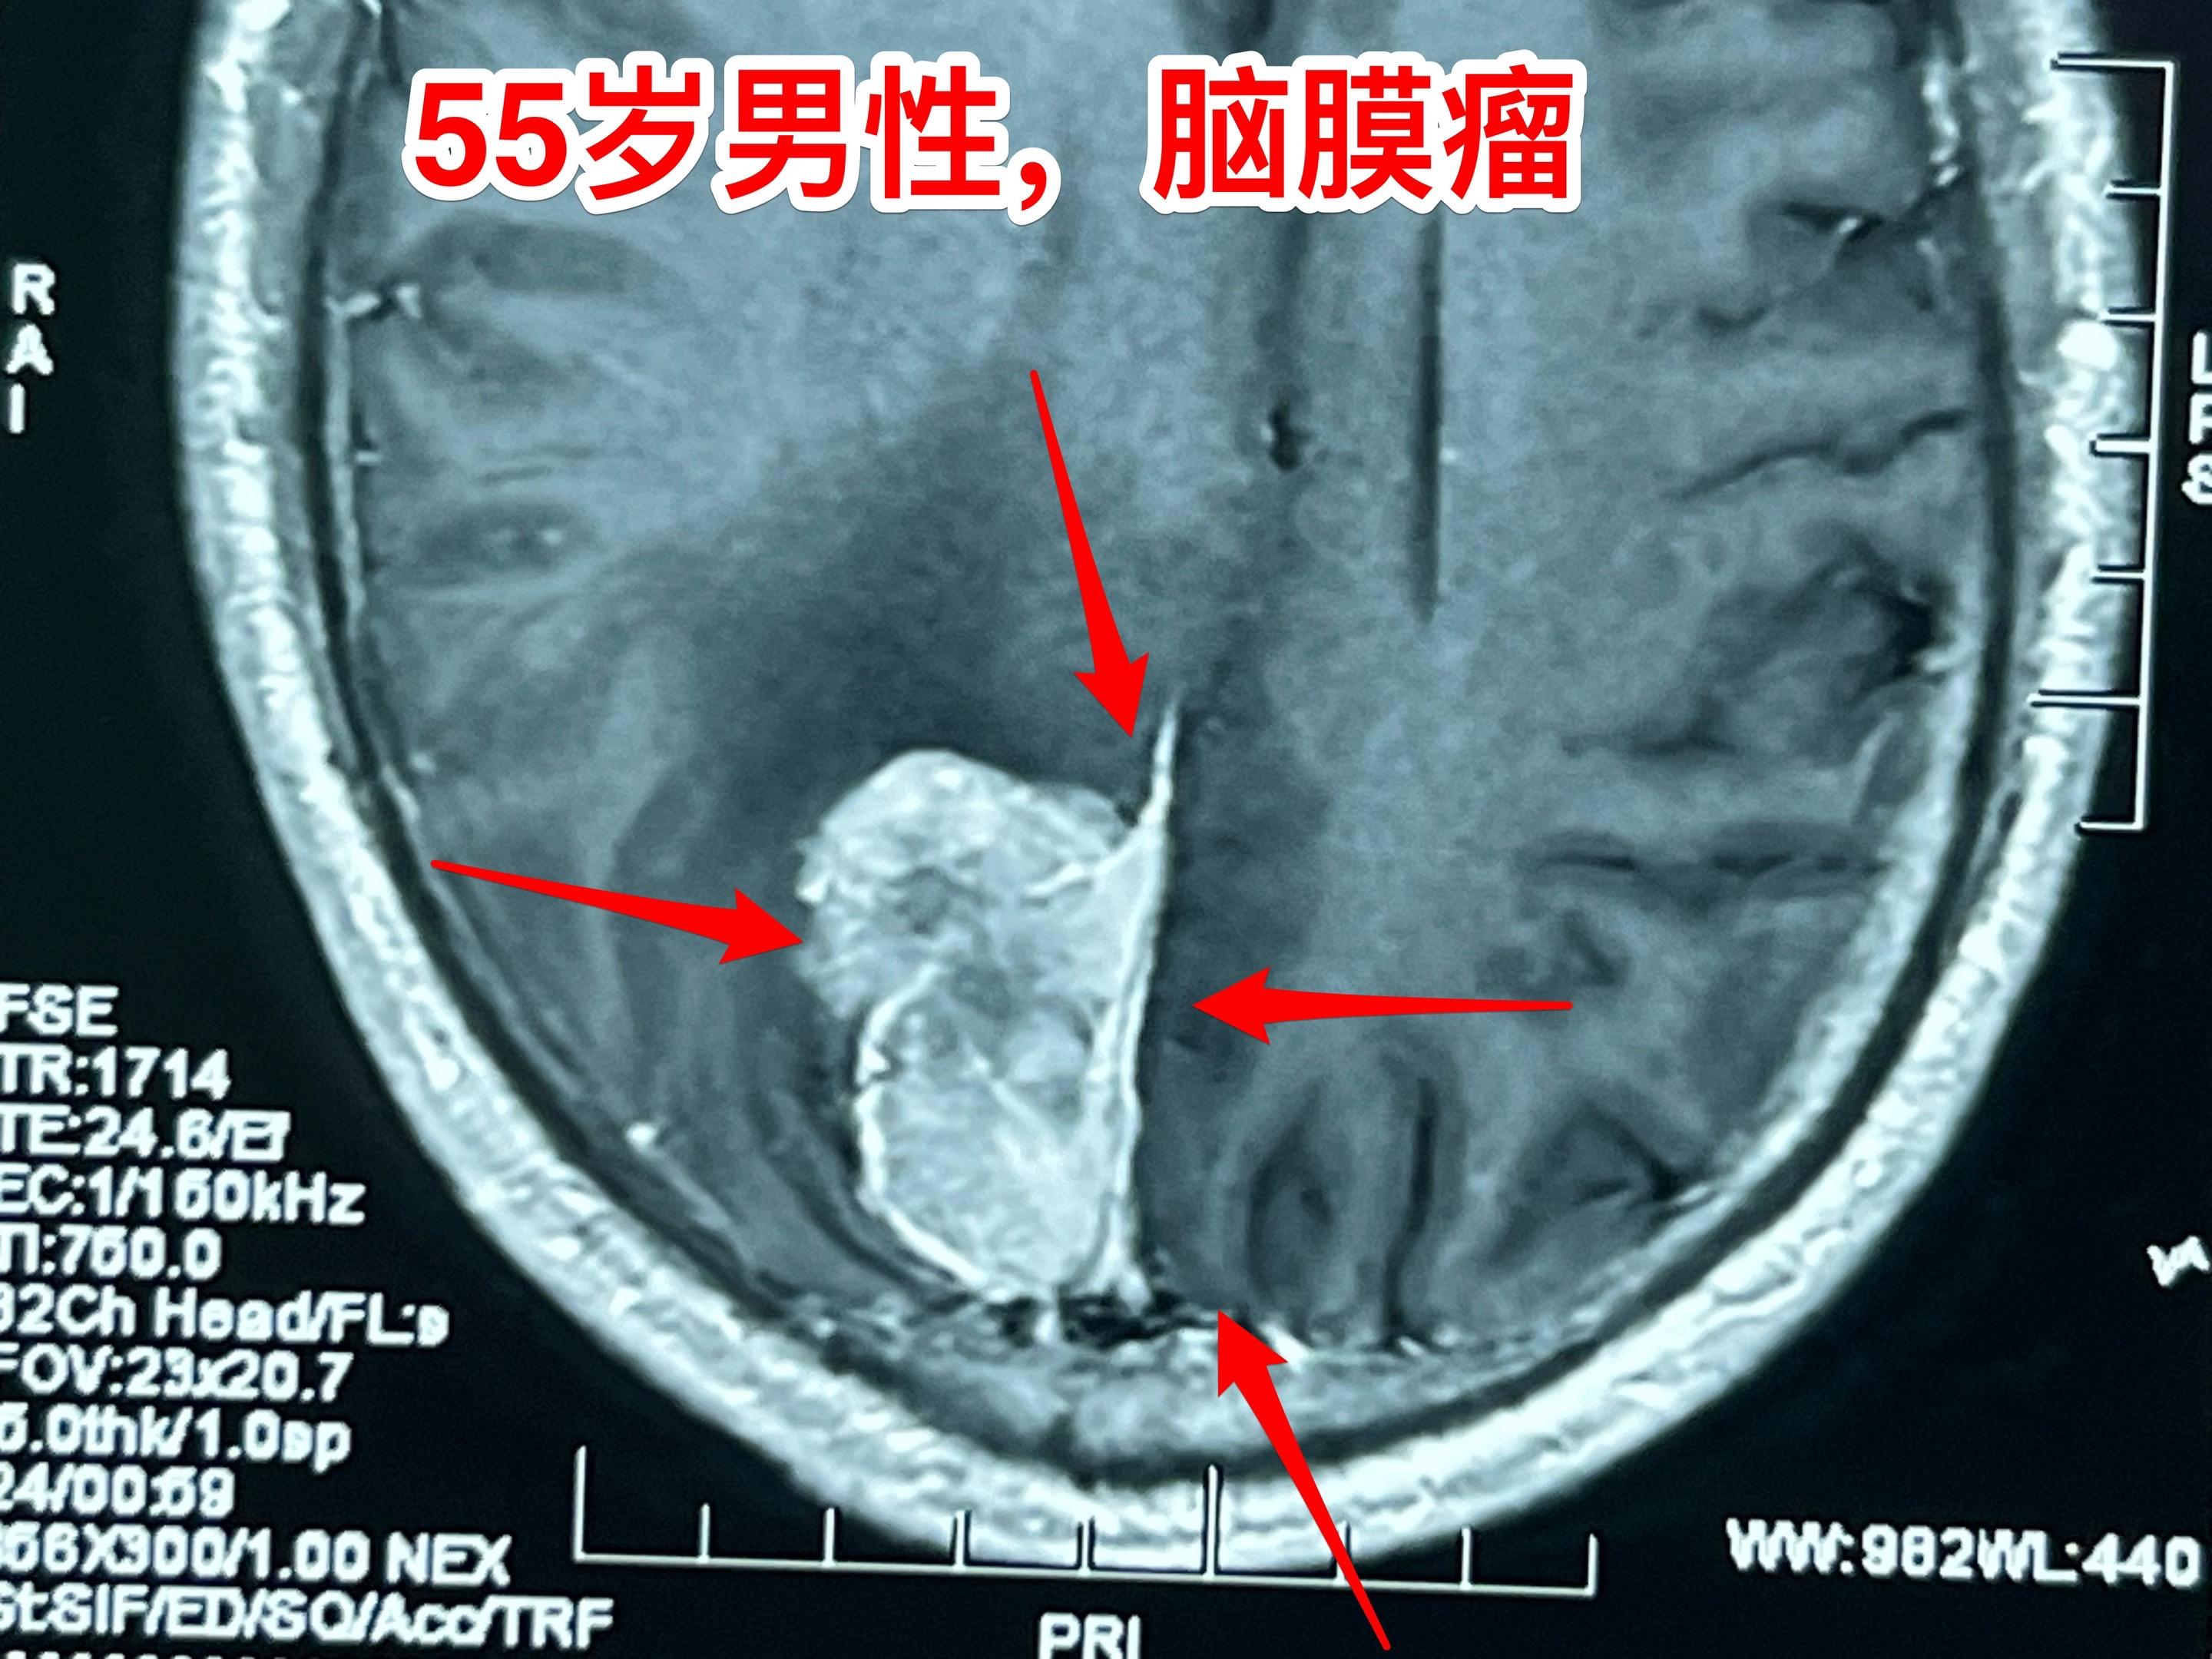

55岁男性因头痛发现脑膜瘤。脑膜瘤是良性肿瘤,如果有症状的话,就应该作手术切除肿瘤。彻底切除脑膜瘤是有希望获得治愈的。 这个脑膜瘤切除手术难度不算太大,今天加班作了手术,晚上就从ICU转回普通病房了。